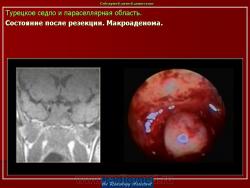

ГМ. Патология области турецкого седла. Набор изображений. +

Патология области турецкого седла.

впервые настолько глубокие изменеия турецкого седла, что даже не требуется дообследование.